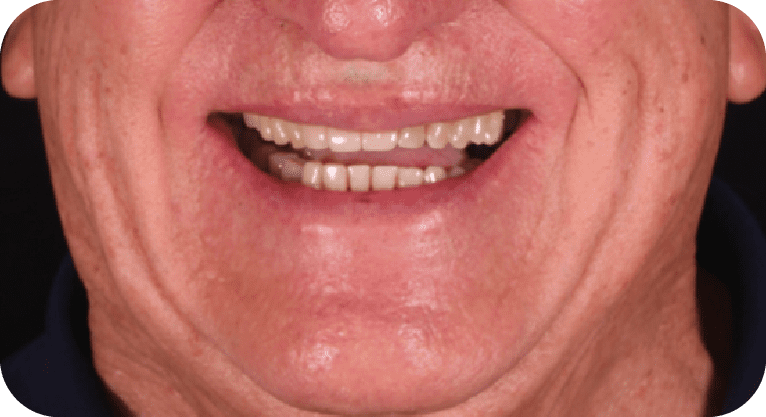

Paciente masculino, “33” años

Tratamiento: Diseño de sonrisa

El paciente presentó inconformidad con la estética de sus dientes anteriores. Tras un diagnóstico clínico y análisis digital, se realizó diseño de sonrisa con carillas de porcelana para corregir forma, posición y tamaño dental, logrando una apariencia armónica y natural que cumplió con sus expectativas estéticas.